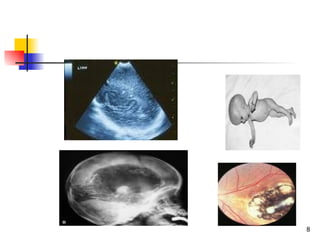

   İntrakraniyal kalsifikasyon, koryoretinit,

hidrosefali olguların %60’ında tespit

edilmektedir

USG’de:                    Kordosentez:

   Plasental kalınlaşma      Toksoplazmozise

   Hidrosefali veya           özgü IgA, IgM veya

mikrosefali                IgE

   Hepatik veya              Kobay inokülasyonu

intrakraniyal              ile T. gondii

kalsifikasyon              izolasyonu